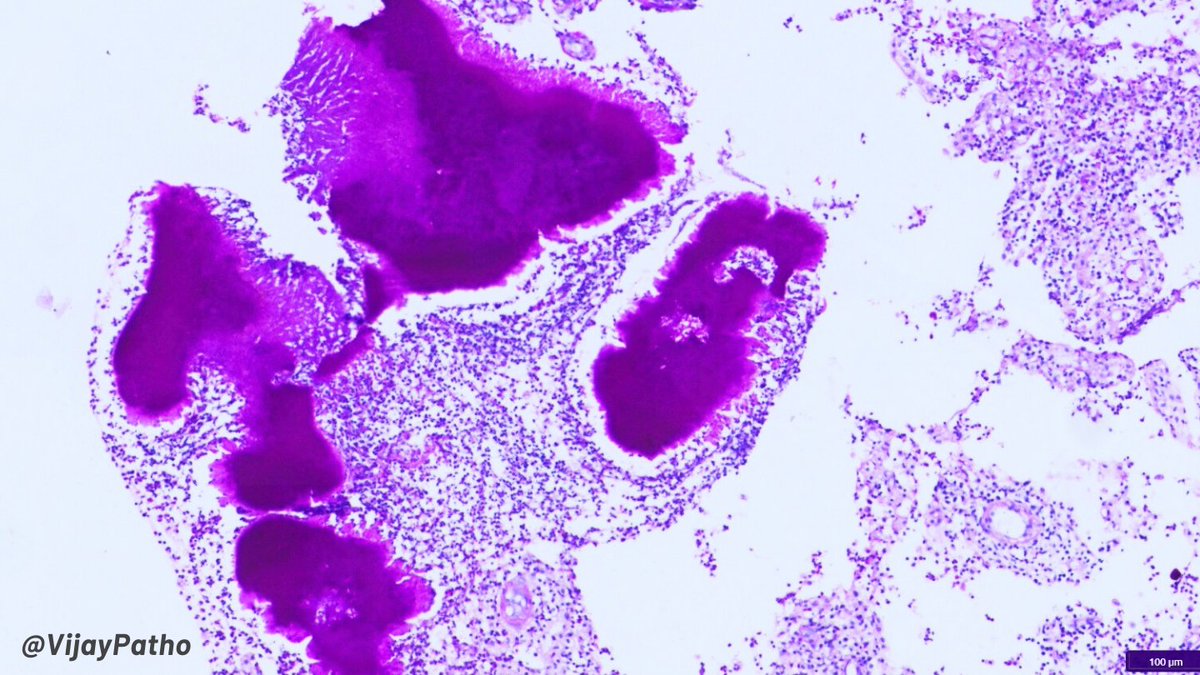

Mucinous lesions of the endometrium -60 yo female with hydrometra -Endometrial biopsy with glands with mucin cells, goblet cells and red granules (last 2 pics) IHC: ER neg. PAX-8, CK7, CDX-2 patchy positive. CK20 focal +. p53 wild type. Chromogranin focally + How would you sign…

-60 yo female with hydrometra

-Endometrial biopsy with glands with mucin cells, goblet cells and red granules (last 2 pics)

IHC: ER neg. PAX-8, CK7, CDX-2 patchy positive. CK20 focal +. p53 wild type. Chromogranin focally +

How would you sign…